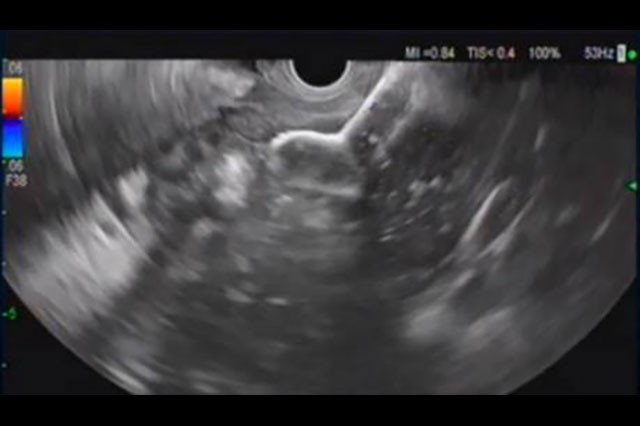

Physicians with experience placing the 20mm AXIOS™ Stent discuss in what clinical situations they chose to opt for the larger stent and what potential benefits may be associated with the use of a large diameter.